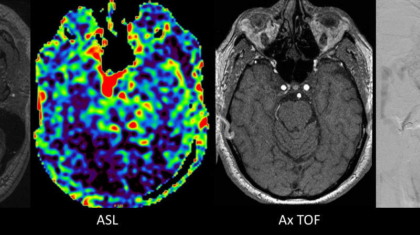

A 71 year old male presented with 1-year history of ocular symptoms (diplopia, proptosis, episcleral congestion).